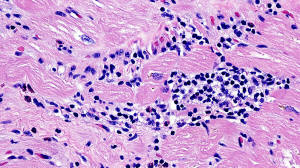

Figure B: H&E staining (20x)

Histology: H&E stains ( Figures A, B, C, and D) show Chronic interstitial myocarditis with mild to moderate infiltration of interstitial spaces with mononuclear cells admixed with scattered eosinophils and diffuse fibrosis.